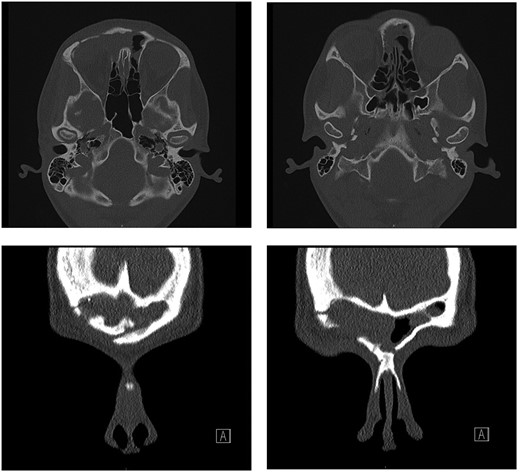

Computed tomography (CT) of the sinuses revealed proptosis, downward displacement and flattening of the upper surface of globe because of a recurrent right frontal sinus OF (Fig. 1).

Ossifying fibroma in the right frontal sinus involving anterior and lateral frontal sinus walls, and orbital floor.

Post-operatively, the patient recovered well with no complications. Examination of the eye four weeks after surgery showed significant improvement—visual acuity was 6/6 on the right, 6/5 on the left. The visual acuity improved to 6/6 on both sides 10 months after surgery; however, there was a residual hypotropia. A repeat CT scan at 4 months post-surgery displayed no bulky residual disease and improvement of proptosis (Fig. 3).

Repeat CT scan at 4 months after surgery, demonstrating no residual disease and radiological improvement of proptosis.